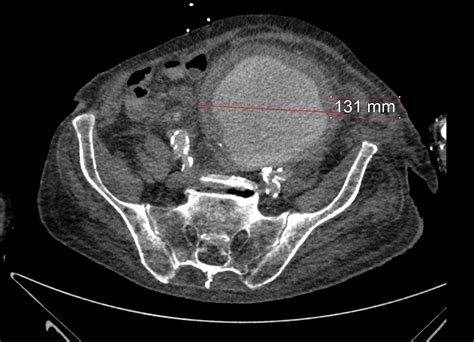

• Computed Tomography Angiography (CTA): This imaging test provides detailed images of the blood vessels and can help determine the size and location of the aneurysm.

• iliac artery aneurysm radiology